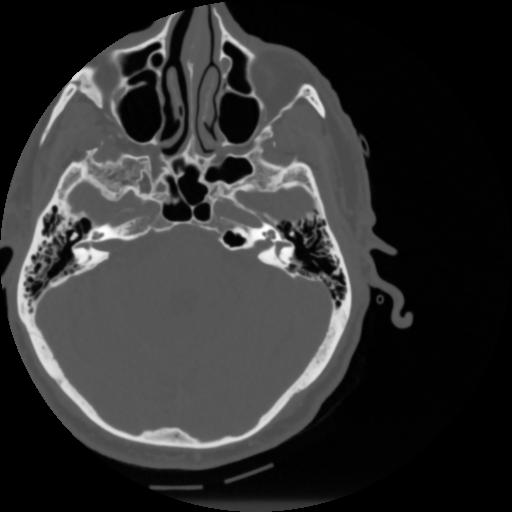

4 CEREBRO,,Vol,0.5,CEREBRO,,